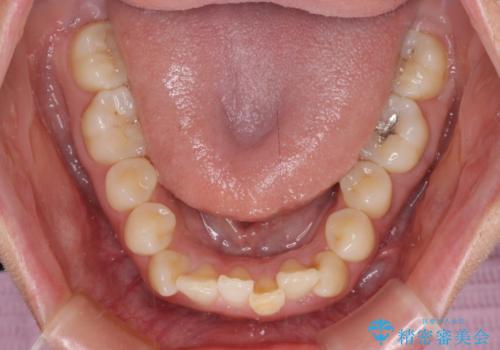

前歯のクロスバイト 目立たないワイヤー装置で速やかに矯正治療

- 前歯のクロスバイトを気にして来院された患者様です。

治療方法としては、マウスピース矯正(インビザライン)でもワイヤー矯正でも、何でも対応可能ですが、自己管理の煩わしさがなく、治療期間の目処を立てやすい表側のワイヤー矯正にて治療を行うこととしました。